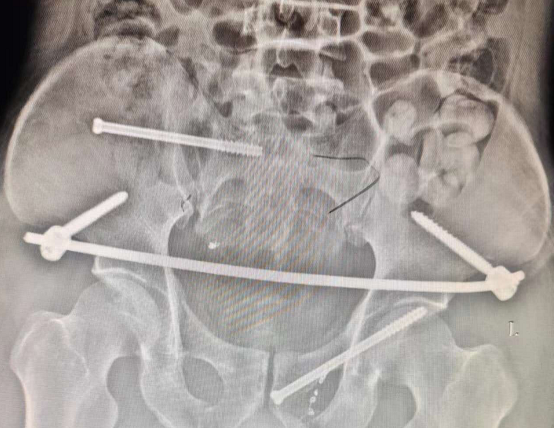

因患者骨盆环稳定性完全破坏且尿道损伤已行过开放手术治疗,后续针对骨盆骨折问题,故选择微创手术,减轻患者创伤疼痛,术中行骨盆闭合复位徒手经皮耻骨支逆行通道螺钉内固定技术,骨盆闭合复位infix微创固定技术,骶髂关节不稳闭合复位通道螺钉固定技术。此三种手术方式同时运用在同一个患者上,操作难度极大,风险系数极高,对手术医生有极高的理论、经验及操作要求。手术圆满成功,患者伤口缝合面小,现患者正接受系统的康复功能训练。

术后 影像显示

骨盆微创手术与开放手术相比具有切口美观、软组织损伤小、出血量少、术后疼痛轻、功能恢复快等优点。骨盆各种通道螺钉固定技术的开展,进一步提高了贵州医科大学附属白云医w院骨科团队在骨盆骨折微创手术治疗方面的技术水平,标志着贵州医科大学附属白云医院骨科治疗水平又迈上了一个新台阶。